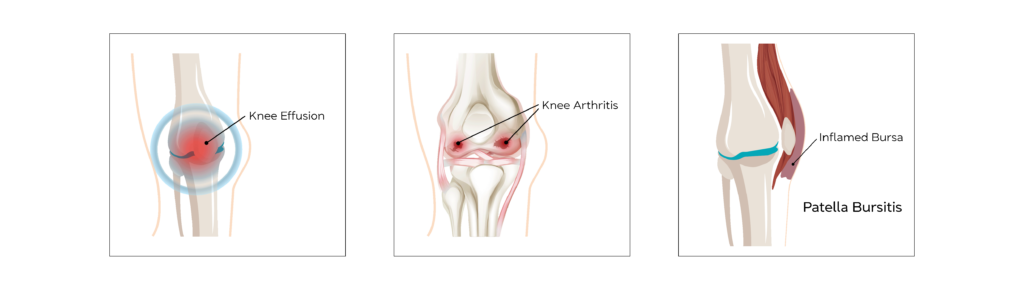

Knee Effusion

Knee joint Effusion is when excess fluid accumulates in or around the knee joint. A normal average knee joint has 4-6 mls of synovial fluid. It can result from both trauma and non-traumatic causes such as inflammation.

It is a relatively common condition.

The main symptoms of knee effusion are swelling and redness of the skin around the kneecap, stiffness in the joint and difficulty straightening or putting weight on the knee, alongside a pain.

Ultrasound can measure the extent of an effusion and can be used to drain the fluid using a needle followed by an injection of steroids to help prevent recurrence especially in inflammatory conditions.

Patella Bursitis (Supra/Pre/Infra)

Inflammation of normal fluid filled spaces around the knee joint.

Patella Bursitis can be common in people with repetitive work tasks that result in kneeling for prolonged periods.

Common symptoms of patella bursitis are pain during activity, rapid swelling in the front of the kneecap, tenderness and a slight rise in temperature of the area.

If symptoms are not relieved with simple anti inflammatory medications and activity modification, ultrasound guided aspiration followed by steroid injections have proven to give relief of symptoms

Knee Arthritis

Osteoarthritis is a painful degenerative condition affecting any joint with articular cartilage due to gradual wear and tear of the articular cartilage, which protects the bone ends.

It affects around 18% of the population with 1 in 5 above the age of 45 seeking medical help.

Main symptoms are pain and swelling of the knee with activity and relieved by rest. Early morning stiffness in the initial stages which can progress to constant severe pain, progressing to deformity of the knee joint.

Osteoarthritis cannot be cured by medications, but injections administered into the joint using steroids or Hyaluronic acid do give short and long term relief of symptoms.